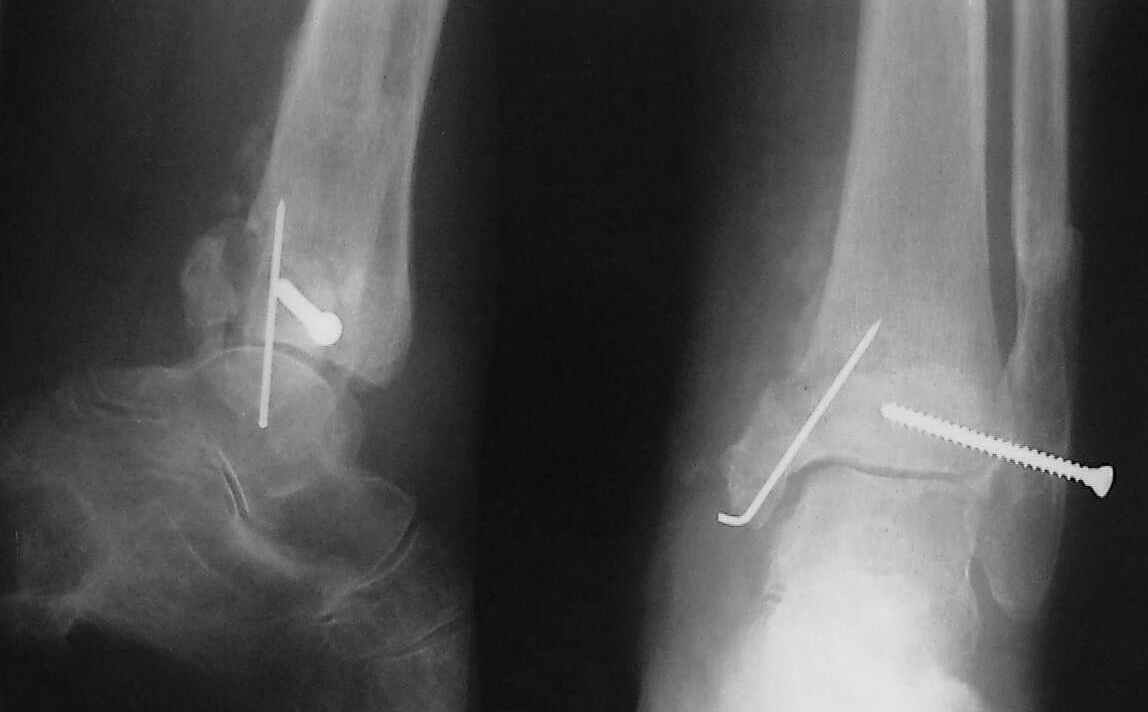

Больная 1936 г.,травма 15 ноября 2003,закрытый трехлодыжечный перелом г/стопного сустава, сахарный диабет.

При поступлении - закрытая репозиция, повторная в связи с большим отеком через неделю, подготовлена к остеосинтезу в первых числах декабря. Заживление без осложнений. Циркулярный гипс - 7 недель, снят,часть спиц удалено 20 февраля т.к.пальпировались под кожей, постепенная нагрузка, проблем нет до середины апреля когда появильсь боли с мед. стороны сустава и локалная гиперемия ( трактовалась как флеботромбоз). Повторное поступление 15 апреля - усиление болей,пов. температура, локально выраженная гиперемия.Локально выделений нет. На RTG - деструкция в области мед лодыжки и заднего края. Сахар крови умеренно повышен. Как трактовать проблему, какой диагноз и тактика лечения? Заранее спасибо, Владимир.

Я бы проблему трактовал как изначально нестабильный и нефункциональный остеосинтез с длительной иммобилизацией у больной с сахарным диабетом, ангиопатией и остеопорозом.

Диагноз я бы поставил: неправильно срастающийся перелом обеих лодыжек и заднего края ББК. Ложный сустав мед. лодыжки? Хронический вялотекущий остеоимиелит голеностопа. Сопутствующий - СД, диабетическая ангиопатия 2.

А почему изначально не сделали хоть по Веберу? В чём смысл 6-ти скусанных спиц? И для чего ввинтили несоответствующий методике шуруп в нижнюю треть остеопорозной, практически отсутствующей лодыжки?

Ретроспективно, на Ваш взгляд, что изменилось бы при остеосинтезе более массивными имплантами?(выбор в пользу спиц как раз и был из-за минимального объема оставляемых имплантов) Иммобилизация 7 недель это очень длительно? Результат на 4 RTG - в чем нефункциональность? - согласен, что репозиция заднего края не была достигнута. Какие признаки ложного сустава мед. лодыжки ?